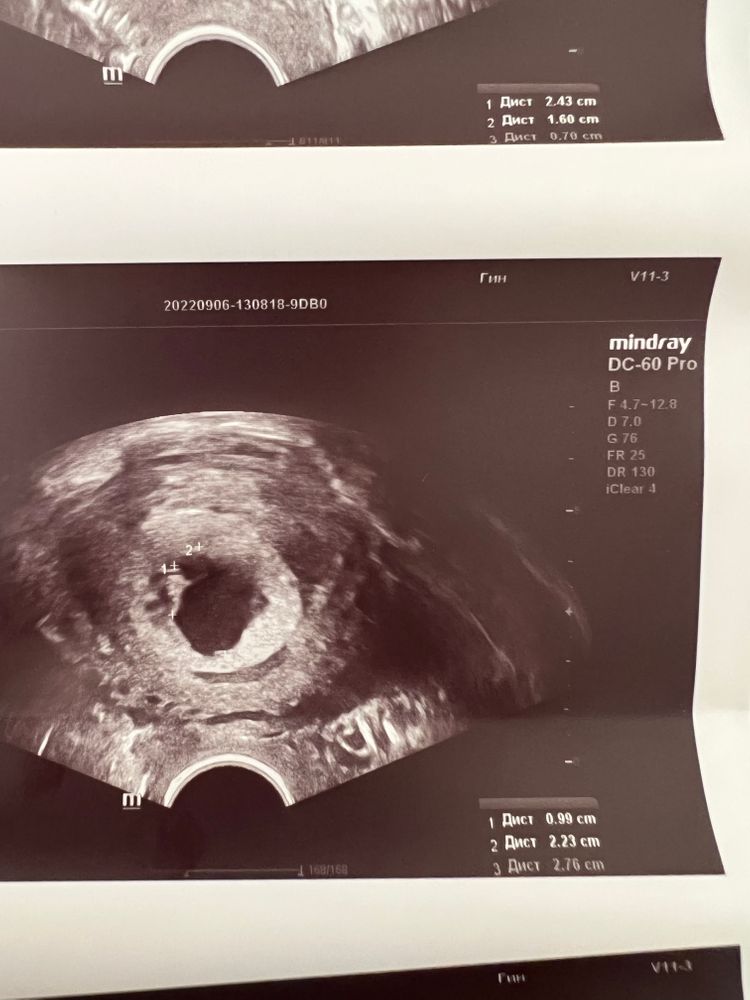

Девочки посмотрите пожалуйста какой здесь свд?

в заключение написано 24 мм, но по моим подсчетам 20мм?

Ангелина, разве не нужно 3 величины сложить и разделить на 3???

Светлана, нет конечно. Размер определяют по наибольшей диагонали.

Ангелина, нет же… это свд пя… именно у него смотрят средний размер пя..

Светлана, ну у вас на снимке замеры